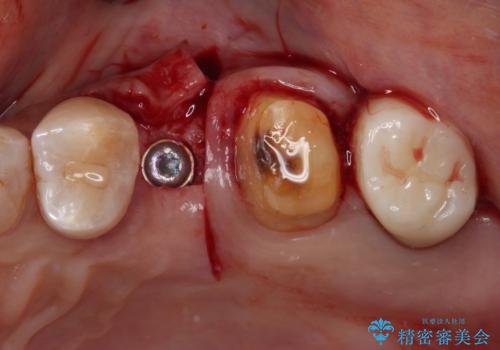

他にも、咬合時に痛みを感じる歯や、欠損により咬みにくい奥歯などをインプラントを用いて治療を行うこととしました。

右下は、残存歯の状態があまり良くなかったため、今後抜歯となったことを想定して、最後臼歯のインプラントを決定しました。